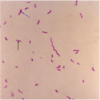

Clostridium perfringens

gram + rods